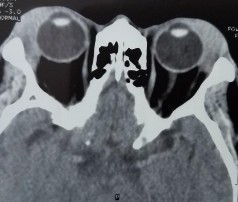

Bệnh nhân nam, 41 tuổi, MP: lồi mắt

Chẩn đoán MP: U hỗn hợp tuyến lệ lành tính

Bệnh nhân lồi mắt xuất hiện 3 năm, tăng nhanh trong vòng 1 năm trước vào viện, đẩy nhãn cầu xuống dưới (A). Hình ảnh cắt lớp vi tính có khối tăng ti trọng, bờ dày đều, kích thước 27 x 38 mm (C, D). Bệnh nhân được phẫu thuật cắt bỏ u cả khối gồm cả vỏ (E). Kết quả giải phẫu bệnh là hình ảnh biểu mô và trung mô của u hỗn hợp tuyến lệ lành tính (F: H&E x 100).